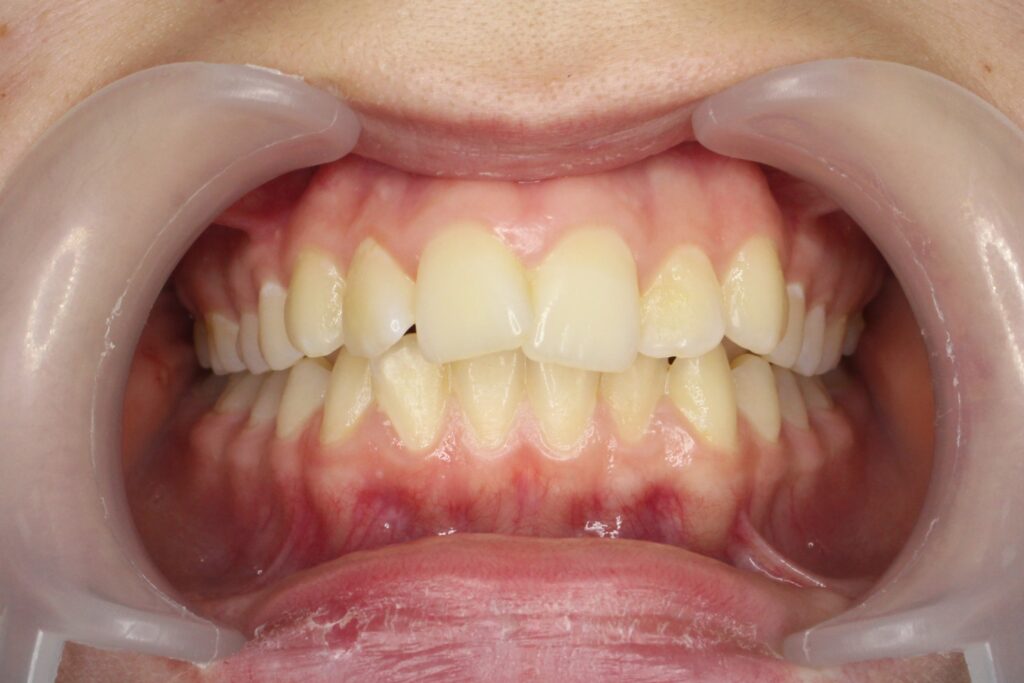

пациент после ортодонтического лечения